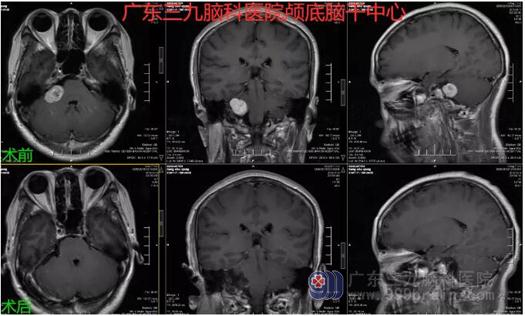

图3:术前术后MR示呈术后改变,右侧桥小脑角区病变已切除。